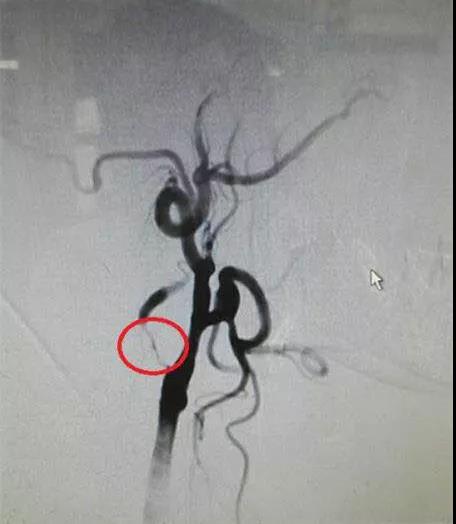

患者术前脑血管造影图,显示右侧颈内动脉重度狭窄>98%,接近闭塞